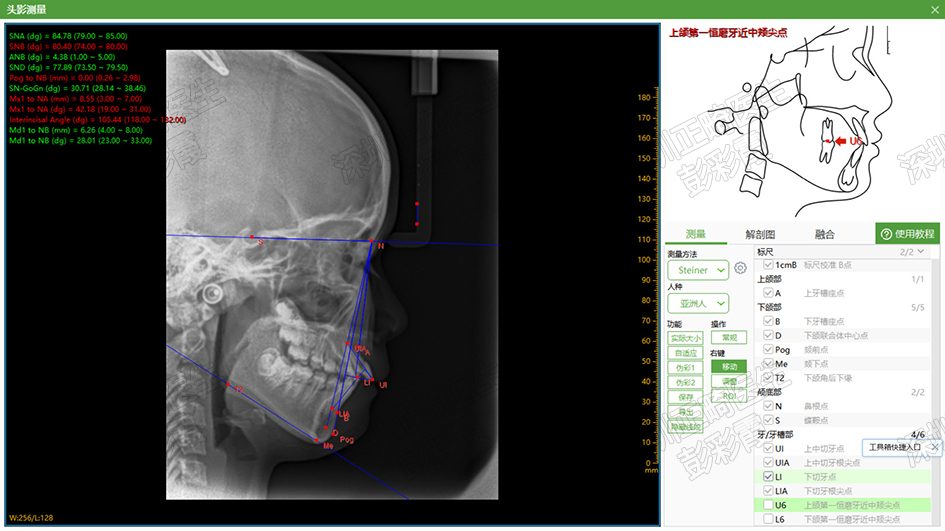

医生需要综合分析患者的面相、X片、牙齿情况,得出诊断及问题列表,从而设计方案(图1); 其中X片(图2)和模型(无示例)均需要经过数字化软件进行测量,得出精确数据。

图2 侧位片的头影测量分析